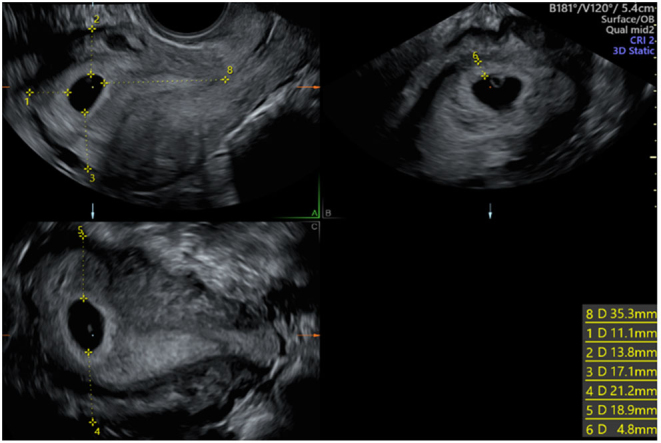

Abstract: Embryo implantation is vital for successful conception but remains to be fully understood. Trophoblast invasion is key for implantation, with anchorage and depth of placentation determined by its extent. There is a dearth of synchronous information regarding IVF, implantation site, and trophoblastic thickness (TT). Our aim was to determine whether pregnancy implantation site and TT, had an impact on outcomes of IVF pregnancies. This prospective observational study was undertaken at a tertiary referral UK fertility unit over 14 months, collecting data on implantation site and TT from three-dimensional (3D) images of the uterus following early pregnancy scan. Of the 300 women recruited, 277 (92%) had live births, 20 (7%) miscarried, 2 (0.7%) had stillbirths, and 1 (0.3%) had a termination. Significantly more pregnancies that resulted in miscarriage (7/20, 35%) were located in the lower uterine cavity when compared to ongoing pregnancies (15/277, 5%) (P < 0.01). TT was significantly higher in ongoing pregnancies when compared with those who miscarried (7.2 mm vs 5.5 mm; P < 0.01). Implantation in the lower half of the uterine cavity and decreased TT are significantly associated with an increased rate of miscarriage. Identification of those at risk should prompt increased monitoring with the aim of supporting these pregnancies.

Lay summary: Implantation of an embryo in the womb is vital for a successful pregnancy. We wanted to find out whether findings on an ultrasound scan in early pregnancy had an impact on outcomes of IVF pregnancies. Three hundred women were recruited to the study, 277 (92%) had live births and unfortunately 20 (7%) had a miscarriage, 2 (0.7%) had stillbirths, and 1 (0.3%) had a termination. Many more of the pregnancies that miscarried implanted in the lower part of the womb. The thickness of the infiltration of the pregnancy into the womb was significantly higher in the ongoing pregnancies. We concluded that implantation in the lower half of the womb and reduced infiltration of the pregnancy seen on scan are associated with an increased rate of miscarriage. We propose that when we identify those at risk, we should increase monitoring, with the aim of supporting these pregnancies.